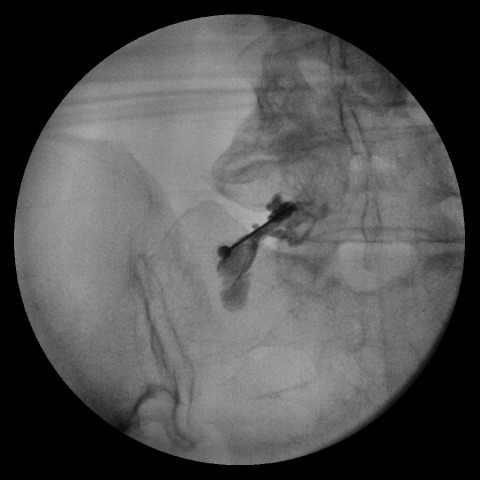

내시경 레이저 디스크 제거술(PELD)

시술과 수술의 중간 정도의 개념으로 직경 1cm 이하의 카메라가 달린 관을 삽입해 화면을 보면서 진행합니다. 1cm 정도의 작은 절개로도 문제 되는 디스크를 제거할 수 있는 시술과 수술의 장점만을 모은 시술법입니다. 수술과 비슷한 방식으로 직접 디스크를 제거하며 압박된 신경이 감압된 것도 확인이 가능합니다.

□ 내시경 화면으로 직접 병변 부위를 보기에 보다 정확하고 안전